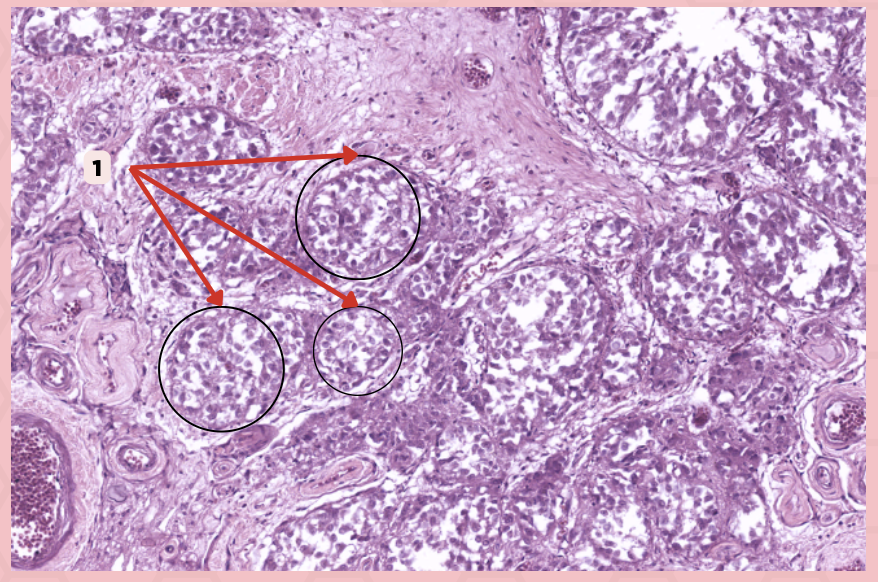

Parathyroid

Identify the specimen.

Chief Cells

Identify the structure labeled as 1. This comprise the majority of cells in the parathyroid gland.

Septa

Identify the structure labeled as 2.

Parathyroid hormones

What hormones are synthesized and secreted by the cell in Pointer #1?

Oxyphil cells

What parenchymal cells in the parathyroid gland only appear shortly before puberty and increase in number with age?

Parathyroid

Identify the specimen.

Chief Cells

Identify the specimen labeled as 1.

Oxyphil Cells

Identify the specimen labeled as 2.

Adipocytes

Identify the specimen labeled as 3.

Capillaries

Identify the specimen labeled as 4.

Newborns

Pointer #2 is hardly present in the parathyroid glands of _____.